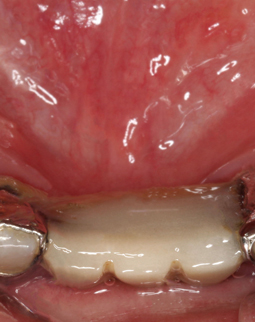

种牙之前我跑了很多医院,最终还是满意这里的种牙方案。说起缺牙,我和一般人还不太一样,我的门牙早些年因为摩托车车祸掉了三颗,和不少纠结“种植牙好还是镶牙好”的人一样,一开始我也因为镶牙便宜,选择了烤瓷牙联桥,几年过去了,发现这个烤瓷牙越来越难用了,一开始吃东西没有异常,这几年老是口臭,而且有金属黑线了,特别影响美观,跟人说话都好像没刷干净牙,我给你们看一下我种牙之前的口内照,有点恶心,请做好心理准备。

值得一提的是,我种牙之前把周围的炎症都提前处理了,做了深层的刮治和洁牙,把牙龈袋和牙缝的结石刮干净,还局部上了些消炎药。你们看下我的牙齿具体情况,黄色的都是牙结石,算严重了,牙龈也有些红肿对不对?很大一部分原因是因为那个烤瓷牙联桥导致的。